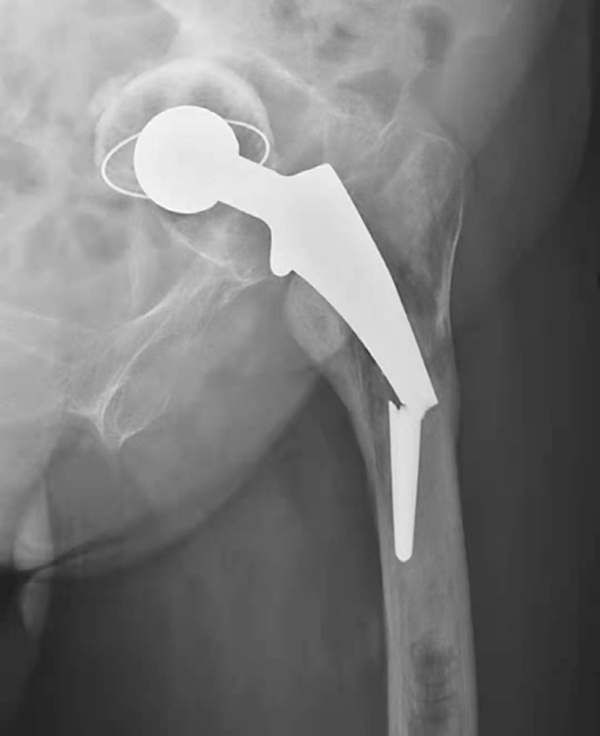

图5 左侧人工髋全脱位

平片,示左侧人工股骨头与髋臼关系失常,人工股骨头脱出髋臼向外上方移位